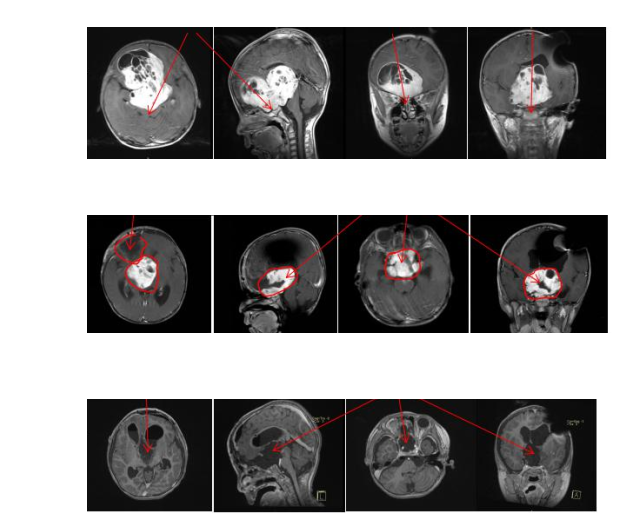

手術(shù)順利:顯微手術(shù)切除率≥ 大概率!!! 通過額骨顱骨開顱術(shù)和大腦半球間穹窿入路腫瘤切除術(shù)直至Monro孔(室間孔),并沿著腦室壁向中腦行進(jìn)。右側(cè)視神經(jīng)被腫瘤浸潤包裹,但是左側(cè)視神經(jīng)被小心地從腫瘤腫塊中剝離出來,垂體腺和垂體柄也被小心的保護(hù)起來。沒有術(shù)中并發(fā)癥。

術(shù)前與術(shù)后MR影像對比顯示,切除率> 大概率。